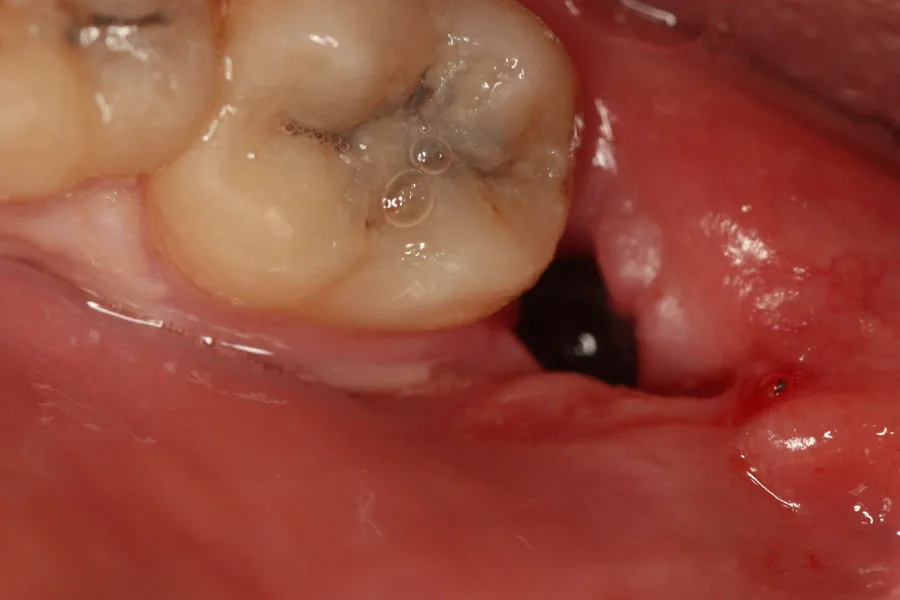

Absolutnie najważniejszym elementem w początkowej fazie gojenia po ekstrakcji zęba jest stabilny skrzep krwi. Działa on jak naturalny opatrunek, chroniąc odsłoniętą kość w zębodole przed infekcjami i stanowiąc matrycę dla nowo tworzących się tkanek. Jego utrata lub niewytworzenie się może prowadzić do poważnych powikłań, takich jak suchy zębodół, o którym opowiem za chwilę. Dlatego tak istotne jest, aby przez pierwsze dni po zabiegu szczególnie dbać o to, by skrzep pozostał nienaruszony.Gojenie dziąsła po wyrwaniu zęba: Harmonogram krok po kroku

Po ekstrakcji zęba proces gojenia dziąsła i kości przebiega w kilku etapach. Zrozumienie tego harmonogramu pomoże Ci lepiej monitorować swój stan i wiedzieć, czego oczekiwać.

- Pierwsze 24 godziny: Powstanie skrzepu i początek regeneracji. To krytyczny czas. Bezpośrednio po zabiegu w zębodole tworzy się skrzep krwi. Jest on niezbędny do prawidłowego gojenia, ponieważ chroni ranę przed czynnikami zewnętrznymi i stanowi rusztowanie dla nowych komórek. W tym okresie możesz odczuwać lekki ból i zauważyć niewielki obrzęk. Kluczowe jest unikanie płukania ust, dotykania rany i intensywnego ssania (np. przez słomkę), aby nie uszkodzić skrzepu.

- Dni 2-4: Stabilizacja skrzepu i szczyt obrzęku. Skrzep krwi staje się bardziej stabilny. Obrzęk może narastać, osiągając swoje maksimum zazwyczaj w trzeciej dobie, po czym stopniowo zaczyna ustępować. Ból powinien być coraz mniejszy i łatwy do kontrolowania za pomocą zaleconych leków przeciwbólowych. Ważne jest, aby kontynuować delikatną higienę jamy ustnej, omijając okolicę rany.

- Pierwszy tydzień (Dni 5-7): Wyraźna ulga i ewentualne zdjęcie szwów. W tym okresie powinieneś odczuć znaczną ulgę. Obrzęk i ból powinny być już minimalne lub całkowicie ustąpić. Jeśli stomatolog założył szwy, najczęściej są one zdejmowane właśnie w tym czasie. Dziąsło nad raną zaczyna się wyraźnie zamykać, przybierając zdrowy, różowy kolor.

- Po 14 dniach: Prawidłowo gojące się dziąsło. Po około dwóch tygodniach dziąsło nad miejscem ekstrakcji powinno być już w dużej mierze zamknięte i wyglądać zdrowo. Tkanki miękkie są zregenerowane, a wszelkie dolegliwości bólowe czy obrzęki powinny być przeszłością. Na tym etapie możesz stopniowo wracać do normalnej diety i higieny, choć zawsze z ostrożnością.